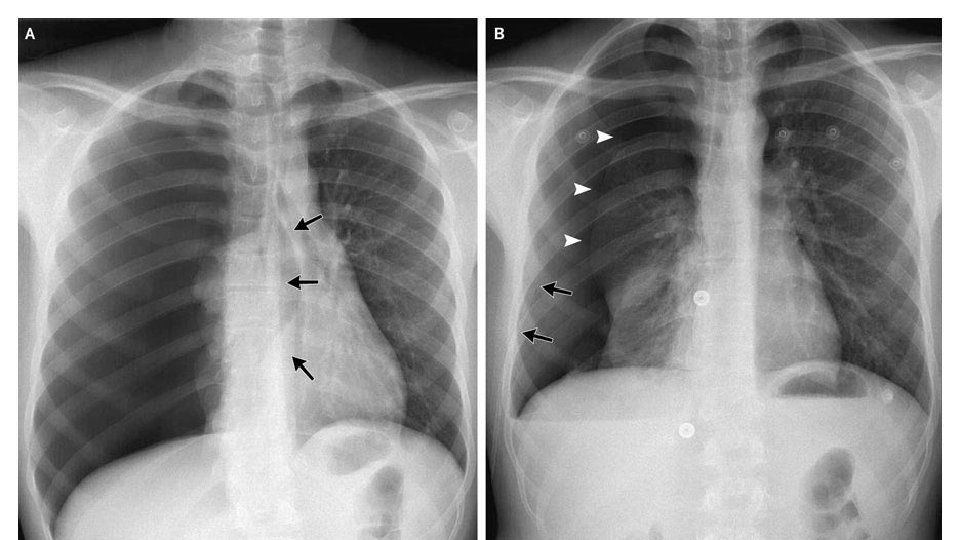

Pneumothorax • Pneumothorax: presence of air in the pleural cavity, commonly known as a collapsed lung, which can occur as a result of a trauma or without trauma • A traumatic pneumothorax can occur from a rib puncturing the lung, gunshot wound, or severe laceration • A nontraumatic pneumothorax occurs due to weakness of the lung tissue • When a pneumothorax occurs, the injured lung moves toward the center of the chest, which put pressure on the heart and other lung • Because only one lung is functioning, the athlete will experience difficulty breathing and will gasp for air • As the athlete continues to breathe, air goes through the hole in the lung and into the chest cavity, which causes the collapsed lung to compress the heart and opposite lung even further

• When there is an imperfection in the tissue of the lung, it can break and cause the lung to collapse • There doesn’t have to be any impact or illness Spontaneous Pneumothorax associated; the athlete may appear healthy in the past and had no previous signs of illness • The athlete will experience difficulty breathing, chest pain, and possibly bluish color of the skin if breathing is poor • The athlete should be placed so that the side with the injured lung is closest to the ground • The AT will treat the athlete for shock and get them to a hospital • Generally will heal itself without surgical interventions

Tension Pneumothorax • An athlete with a pneumothorax may develop a more serious problem called tension pneumothorax • As air leaks out of the collapsed lung and into the chest cavity, it forces the lung to press against the other lung and the heart • If the AT observes the trachea deviated to the side of the throat, they should suspect tracheal shifting • As pressure builds in the chest, the trachea moves away from the side of the pneumothorax • If the trachea moves, the athlete will experience severe respiratory distress • As more air enters the chest cavity, move pressure builds against the heart and uninjured lung • As the pressure mounts, the heart begins to labor as blood flow and breathing are impeded • Death can occur if the athlete is not treated rapidly • If the athlete has an external puncture wound, partially cover it, leaving one side unsealed • Sealing the wound entirely will prevent the inner air from escaping, worsening the condition • With tension pneumothorax, the athlete will experience respiratory distress, absent breath sounds on the injured side, anxiety, and bluish skin color • His pulse will be rapid and weak and blood pressure will drop • As the pneumothorax, worsens, tracheal deviation and neck vein distension will occur, as will bulging of the muscles between the ribs • The AT should place the athlete so that the side with the injured lung is closest to the ground; treat them for shock, and get them to a hospital; put in chest tube and possible surgical intervention